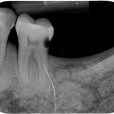

Van de M2 en de M1  (Links) werden  extra rontgenfoto,s gemaakt om  duidelijk te maken dat het niet een maar  twee aparte kiezen betrof .

Duidelijk zichtbaar de wortels van beiden tanden ..

Verder was goed zichtbaaar de vergaande  botontsteking bij de gebroken kiezen .